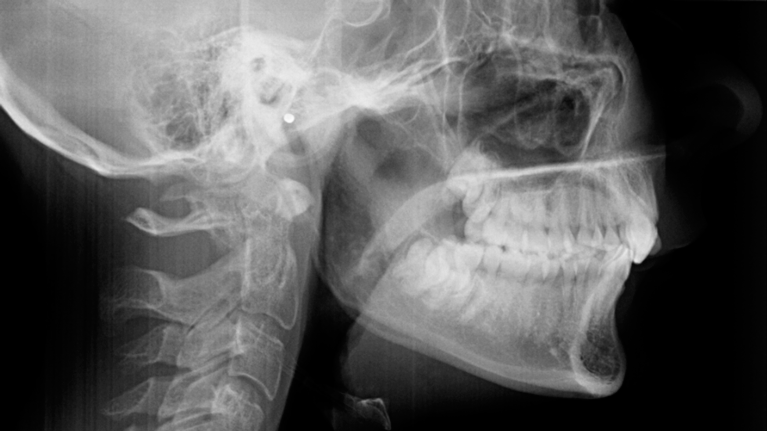

Du skal være færdigudvokset før operationen. Dette undersøger vi vha. et røntgenbillede af din hånd. Du får taget røntgenbilledet enten hos bøjletandlægen eller på Kæbekirurgisk Ambulatorium.